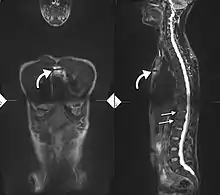

34-year-old male with AS. Inflammatory lesions of the anterior chest wall are shown (curved arrows). Inflammatory changes are seen in the lower thoracic spine and L1 (arrows).

Ankylosing spondylitis is a member of the more broadly defined disease axial spondyloarthritis.[21][22] Axial spondyloarthritis can be divided into two categories: radiographic axial spondyloarthritis (which is a synonym for ankylosing spondylitis) and non-radiographic axial spondyloarthritis (which include less severe forms and early stages of ankylosing spondylitis).[21]

While AS can be diagnosed through the description of radiological changes in the sacroiliac joints and spine, there are currently no direct tests (blood or imaging) to unambiguously diagnose early forms of ankylosing spondylitis (non-radiographic axial spondyloarthritis). Diagnosis of non-radiologic axial spondyloarthritis is therefore more difficult and is based on the presence of several typical disease features.[21][23]